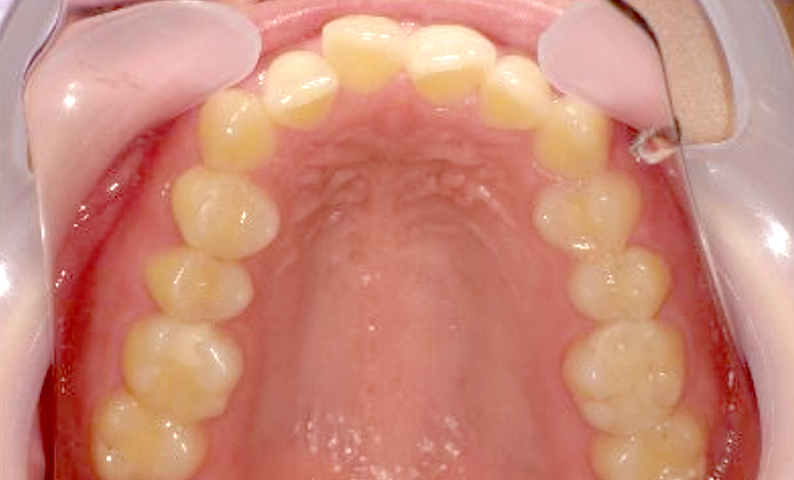

症例_022 上下顎の部分矯正

治療期間:7ヶ月金額:54万円+税女性前歯のガタガタ八重歯一部反対咬合